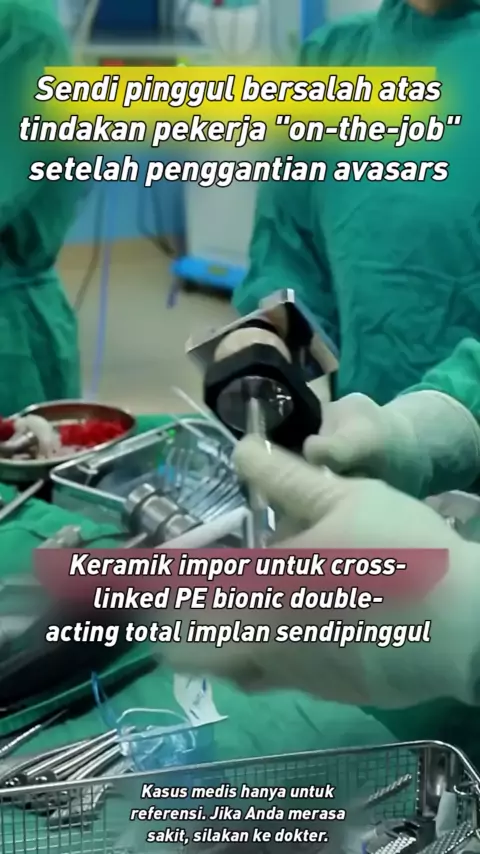

Operasi penggantian Avasars, tentang pekerja "on-the-job" bersalah atas tindakan implan sendi pinggul orang # avasars kepala # Hal-hal yang tidak Anda ketahui di ruang operasi # ruang operasi setiap hari